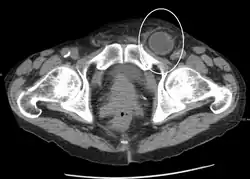

In the diagnosis of abdominal hernias, imaging is the principal means of detecting internal diaphragmatic and other nonpalpable or unsuspected hernias. Multidetector CT (MDCT) can show with precision the anatomic site of the hernia sac, the contents of the sac, and any complications. MDCT also offers clear detail of the abdominal wall allowing wall hernias to be identified accurately.[9]

Femoral